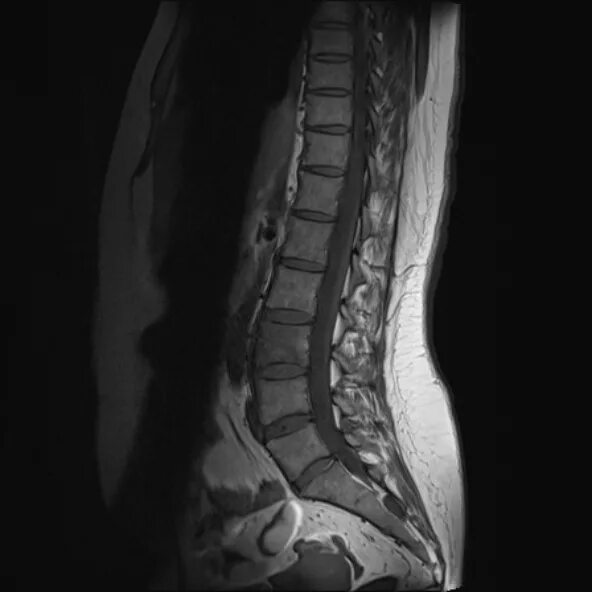

Spine mri